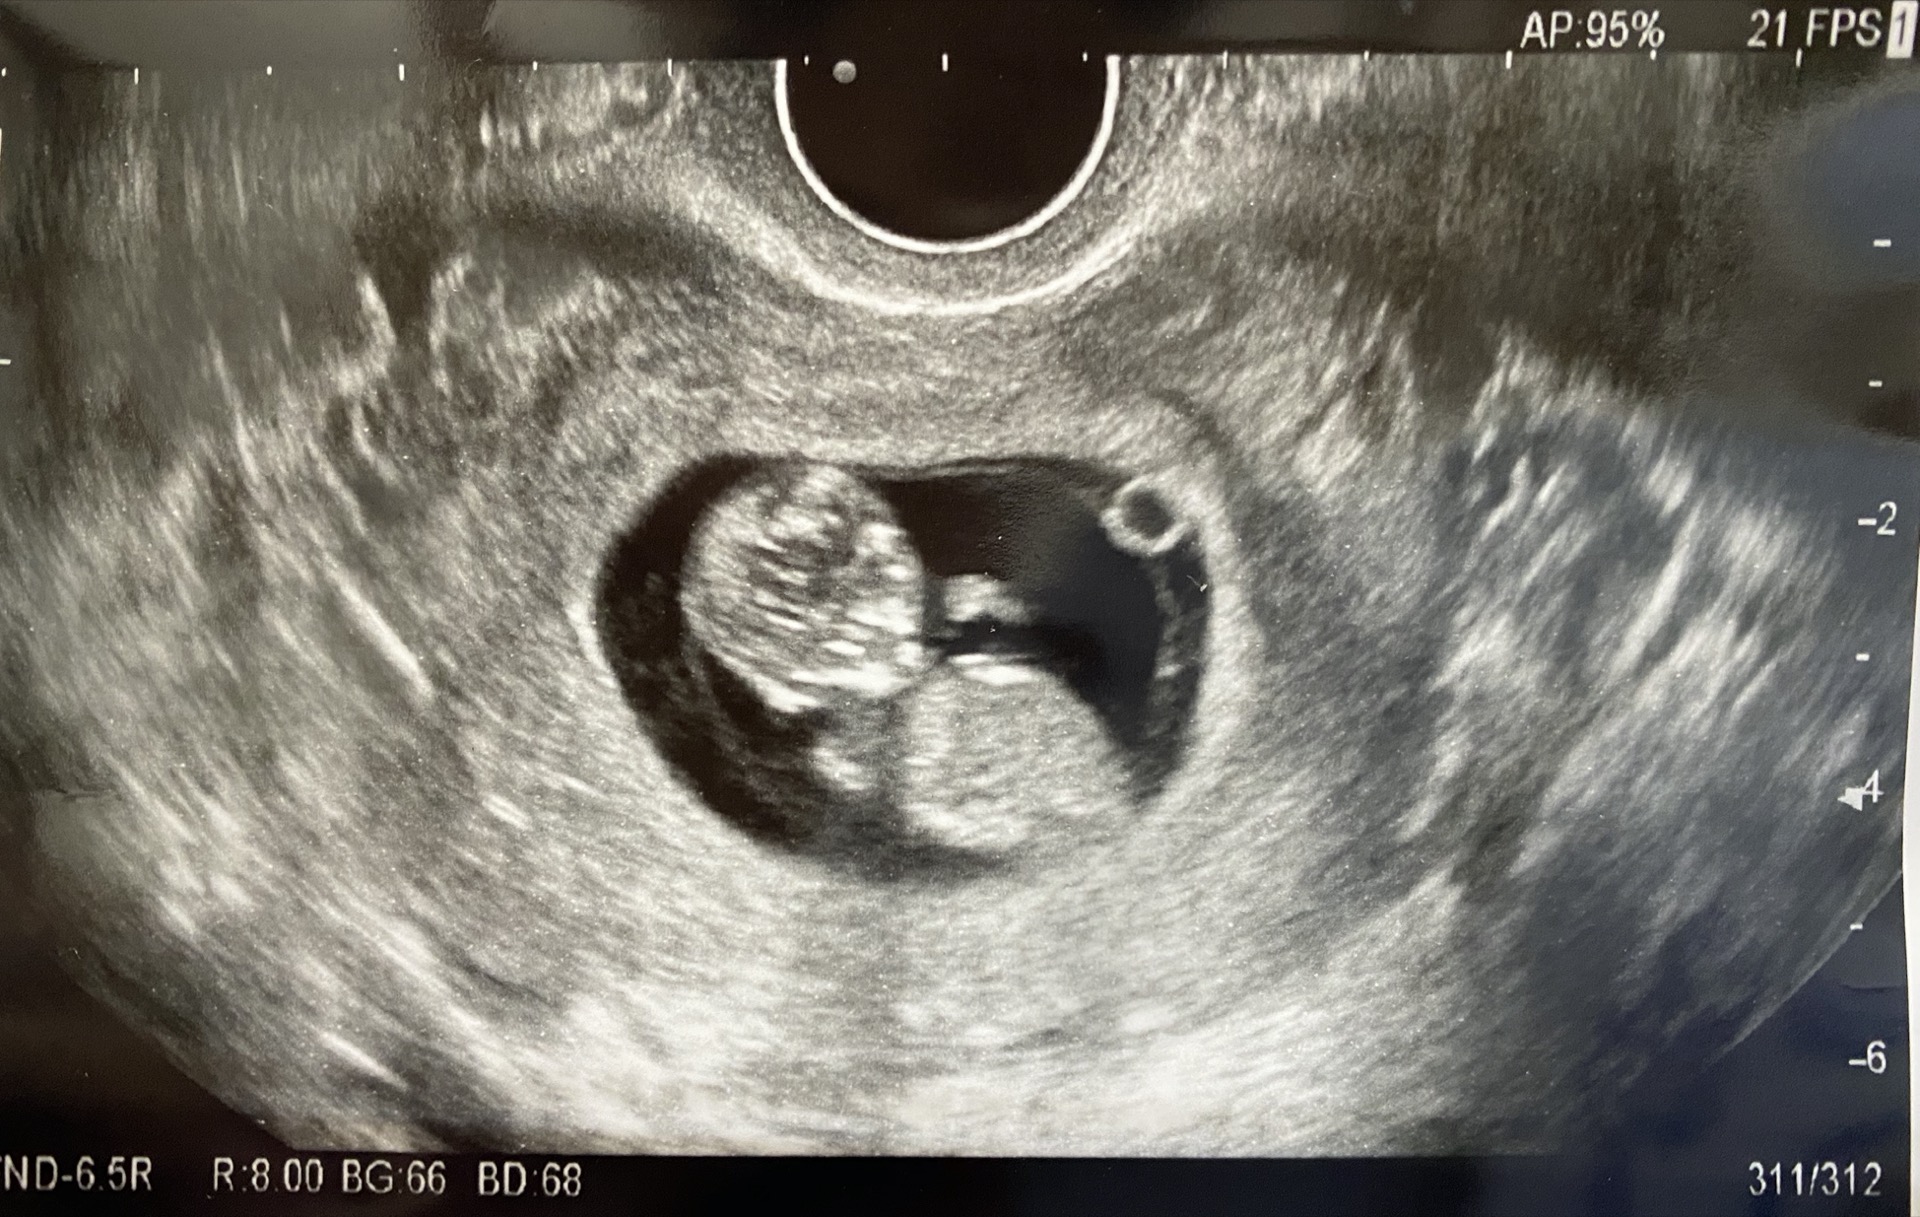

この頃からエコー写真に四肢が写り赤ちゃんらしい姿が見られるように♡